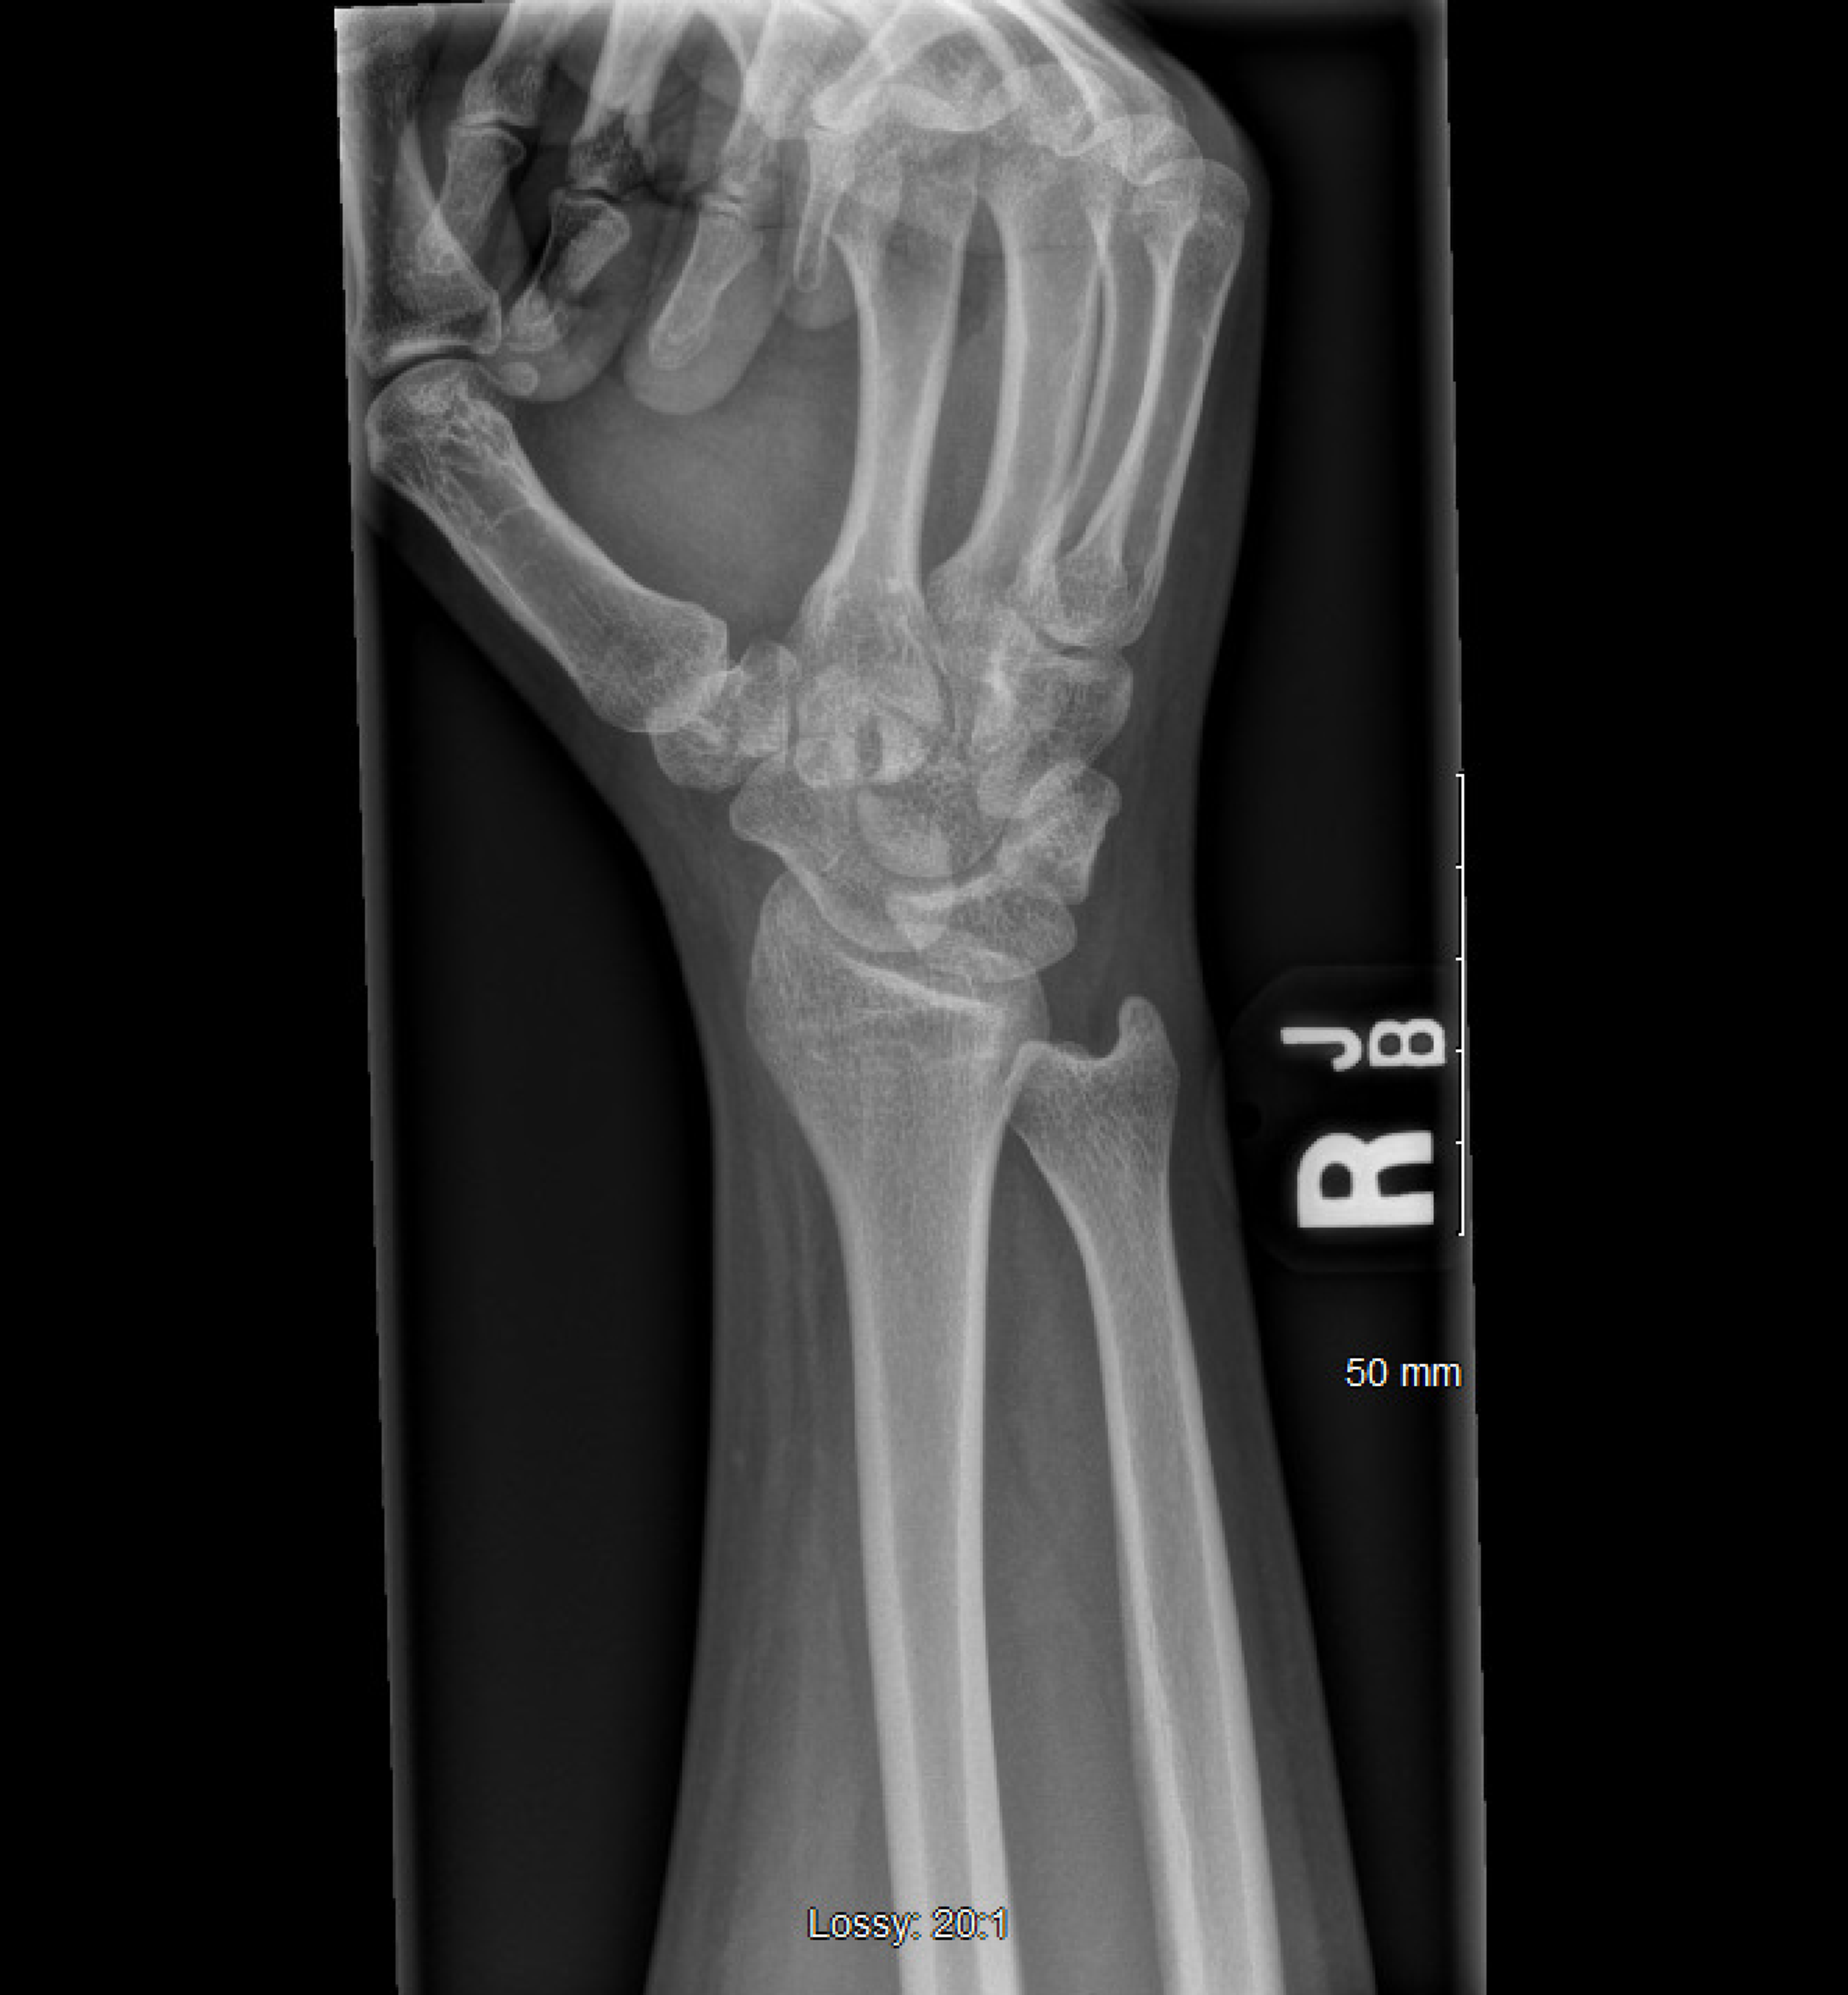

Carpal Tunnel X Ray Projection . This projection is performed most commonly to rule out abnormal calcification and bony changes in the carpal sulcus that may impinge on the medial nerve, as with carpal tunnel. Mri studies following carpal tunnel release may demonstrate an increase in carpal tunnel volume of up to 24%, often accompanied by a change in shape from oval to. This article explains the wrist carpal tunnel view, its indications, and potential uses in investigating specific fractures. It is a cause of significant disability and is one. The lack of symptoms was. Carpal tunnel syndrome was diagnosed by clinical findings and nerve conduction studies. 8x10 cr cassette or dr detector. Carpal tunnel syndrome results from compression of the median nerve (tunnel syndrome) within the carpal tunnel.

Carpal Tunnel X Ray Projection This projection is performed most commonly to rule out abnormal calcification and bony changes in the carpal sulcus that may impinge on the medial nerve, as with carpal tunnel. This projection is performed most commonly to rule out abnormal calcification and bony changes in the carpal sulcus that may impinge on the medial nerve, as with carpal tunnel. Carpal tunnel syndrome results from compression of the median nerve (tunnel syndrome) within the carpal tunnel. 8x10 cr cassette or dr detector. Mri studies following carpal tunnel release may demonstrate an increase in carpal tunnel volume of up to 24%, often accompanied by a change in shape from oval to. It is a cause of significant disability and is one. Carpal tunnel syndrome was diagnosed by clinical findings and nerve conduction studies. The lack of symptoms was. This article explains the wrist carpal tunnel view, its indications, and potential uses in investigating specific fractures.